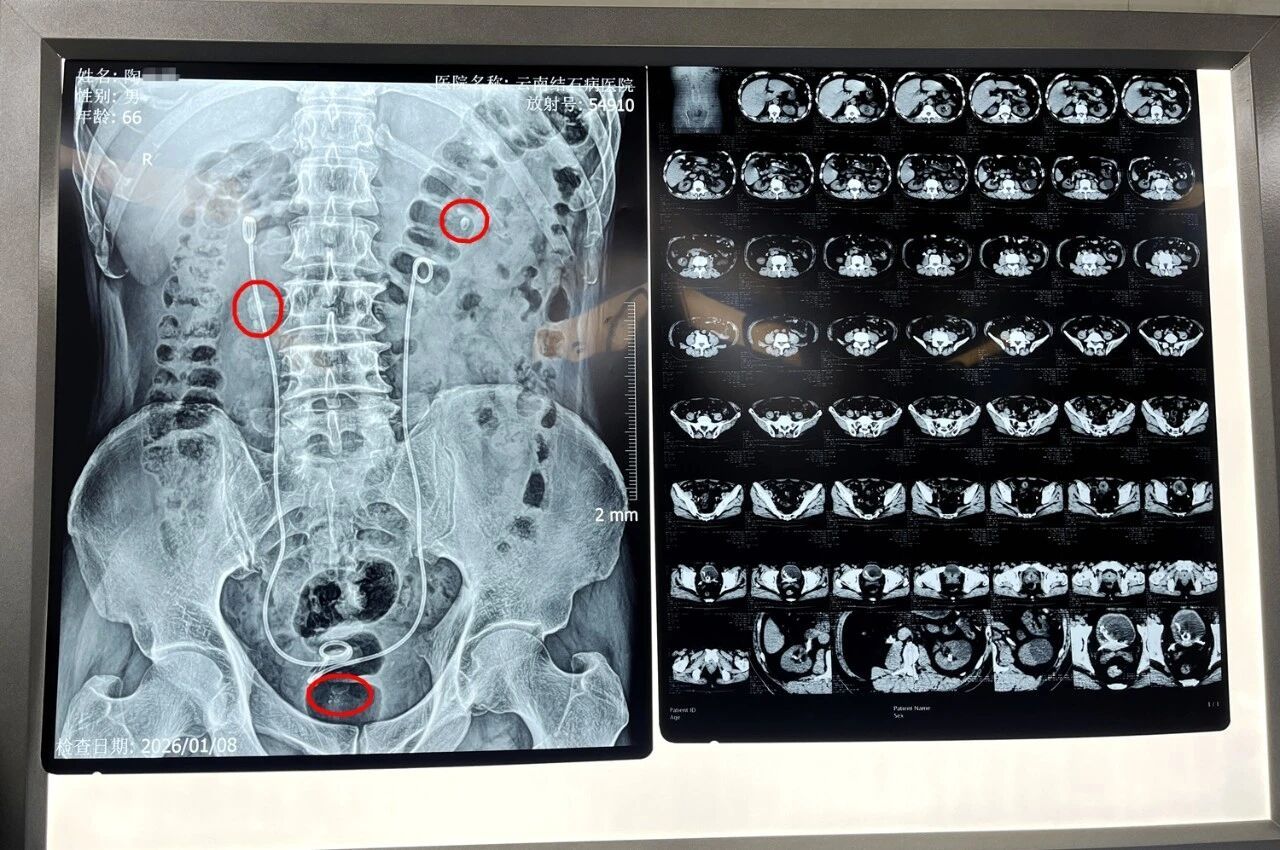

经初步对症处理缓解症状后,为寻求进一步治疗,陶先生慕名来到云南结石病医院。经系统检查,他被确诊为:前列腺增生、右输尿管多发结石伴右肾积水、双肾多发结石、膀胱多发结石,并伴有严重尿潴留。医院首席专家王力教授指出,其前列腺中叶突入膀胱近2厘米,是导致尿潴留的关键原因。

术中,王力教授与黄鸿宾主任先通过瑞梦手术,精准消融患者前列腺左右两叶的增生组织;继而采用双极等离子电切术,将前列腺中叶突入膀胱部分进行精细切除;随后再通过输尿管镜与纤维输尿管镜,将右侧输尿管上段结石、右肾结石及膀胱内结石击碎取出。整台手术历时两个多小时,顺利完成。